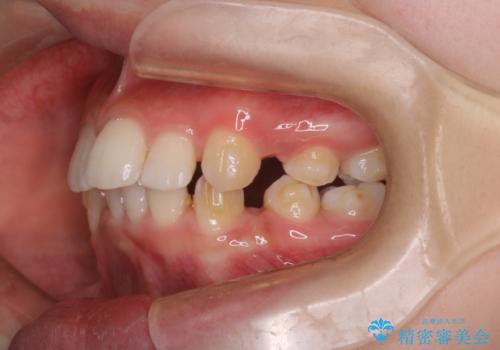

重度の歯のがたつきを、目立たない矯正と抜歯で根本改善

- 前歯から奥歯にかけて歯の重なりが激しい歯のがたつき(重度叢生)を主訴にご来院されました。精密検査の結果、歯が並ぶスペースが大幅に不足しており、歯並びを整え、口元を美しく引っ込めるためには、スペースの確保が必要と診断しました。そこで、上下左右の第一小臼歯(4番目の歯)を計4本抜歯し、そのスペースを利用して歯並び全体を整える抜歯矯正の治療計画を立案。装置には、透明で目立たないインビザラインを採用し、審美性と治療効果の両立を目指しました。

今回の治療では、重度の叢生を改善するため、まず計画通り上下左右4本の小臼歯を抜歯し、歯を並べるための十分なスペースを確保しました。装置には透明で取り外し可能なインビザラインを使用。抜歯によってできたスペースを最大限に活用し、マウスピースを定期的に交換しながら、デコボコを解消しつつ、前歯を効果的に後退させました。

治療の結果、長年の悩みであった重度の歯のがたつきが解消され、口元の突出感も改善。機能的にも安定し、審美的にも美しい、理想的な歯並びを獲得していただけました。